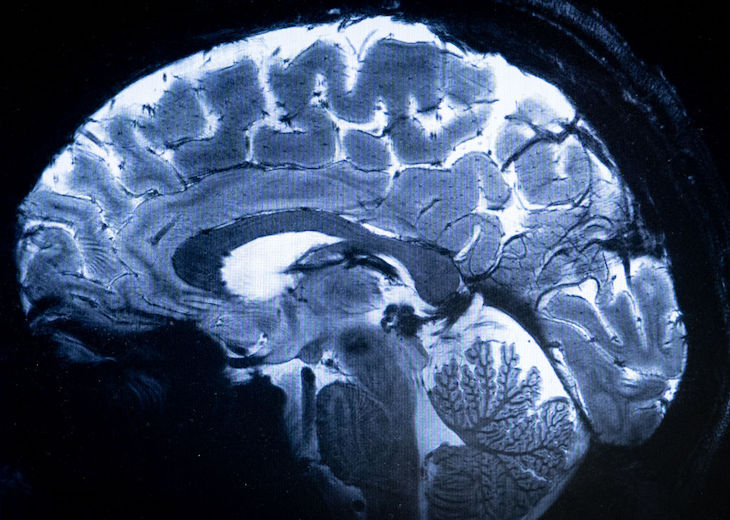

Our ignorance was highlighted recently when Harvard and Google AI experts announced that they had successfully mapped one cubic millimetre of brain tissue (about one millionth of an adult human brain). The imaging and mapping exercise produced 1.4 million petabytes of data. One neuron was found to have over 5,000 connection points to other neurons, of which we have an estimated 86 billion. A member of the Harvard team, Professor Jeff Lichtman, said: ‘We don’t understand these things, but I can tell you they suggest there’s a chasm between what we already know and what we need to know.’

One neuron was found to have over 5,000 connection points to other neurons, of which we have an estimated 86 billion

A minutely controlled ‘rush of blood’ enables the brain to up its game, using an enriched supply of oxygen and glucose, micromanaged by vasodilation within its circuitry. This expands the neural networks, so nerve fibres or axons undergo literal nervous tension. The feelings of being stretched or about to burst a blood vessel may simply describe the brain’s internal processing, doing its job of making connections, delivering fusion and focus. None of this is abnormal, but when the brain makes a particularly big connection, this may well stop us in our tracks and give us a ‘high’, or a eureka moment.